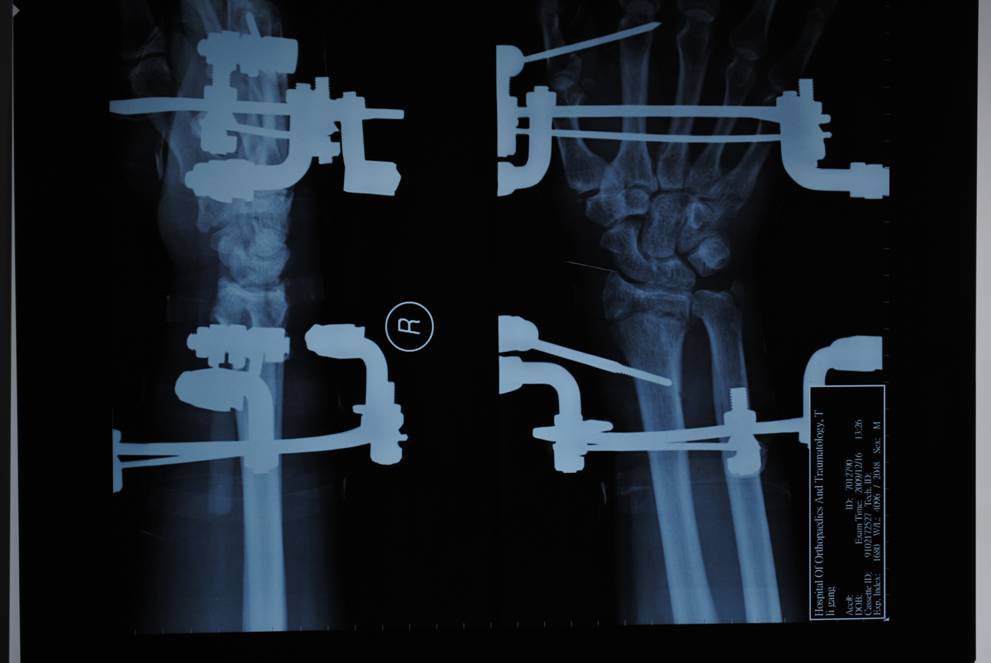

專利腕架

1、一種組合式腕關(guān)節(jié)三維牽引固定架,其特征在于:主要包括一根碳纖維和一根硬鋁連接桿和兩只弧型環(huán),兩只弧型環(huán)沿弧線方向的端面上均設(shè)有多個(gè)通孔,每根碳纖維連接桿的兩端分別鎖緊連接于兩只弧型環(huán)相對(duì)應(yīng)的通孔上,每個(gè)弧型環(huán)上均設(shè)有兩只鎖針螺釘,鎖針螺釘靠近其螺栓部分的端面上均設(shè)有穿針槽,鎖針螺釘?shù)穆菟ń?jīng)螺母鎖緊在弧型環(huán)上,第一克氏針依次穿過第一弧型環(huán)上的第一鎖針螺釘穿針槽、掌骨頸、第二鎖針螺釘穿針槽并由螺母鎖緊第一、二鎖針螺釘?shù)穆菟▽⒌谝豢耸厢槈壕o在第一弧型環(huán)上,第二克氏針依次穿過第二弧型環(huán)上的第三鎖針螺釘穿針槽、橈骨、第四鎖針螺釘穿針槽并由螺母鎖緊第三、四鎖針螺釘?shù)穆菟▽⒌诙耸厢槈壕o在第二弧型環(huán)上。

橈骨遠(yuǎn)端骨折術(shù)前

橈骨遠(yuǎn)端骨折術(shù)后

橈骨遠(yuǎn)端骨折術(shù)前 橈骨遠(yuǎn)端骨折術(shù)后

五研獨(dú)家產(chǎn)品組合式腕關(guān)節(jié)骨外定架,具有專利保護(hù)

組裝簡便,穿針便捷,適合各種橈骨遠(yuǎn)端骨折及腕部矯形。斷端無X線遮擋。